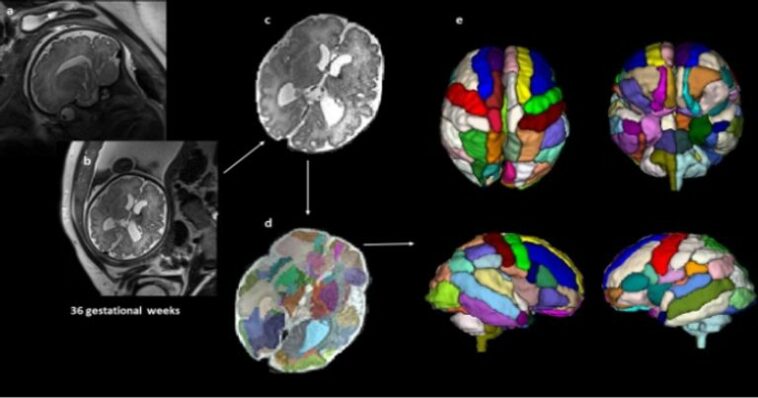

ჰარვარდის მედიცინის მკვლევრები იმასაც ადასტურებენ, რომ ამ მდგომარეობის დიაგნოსტიკისთვის უაღრესად ზუსტი სკანირების სისტემაა საჭირო. ამიტომ მათ ფეტუსზე დაკვირვებისთვის მაგნიტურ-რეზონანსული ტომოგრაფიაა (MRI) გამოიყენეს.

კვლევისას, 39 ნაყოფის ტვინს დააკვირდნენ და მათ სკანირება დაბადების შემდგომაც გადაუღეს. დაბადებამდე გამოკვლეულ 9 ბავშვს მოგვიანებით ASD დიაგნოზი დაუსვეს. კვლევით კი დადგინდა, რომ ბავშვებს, რომელთაც დაბადების შემდგომ აუტიზმი განუვითარდათ, დაბადებამდე ტვინის ინსულარულ ნაწილში გარკვეული ცვლილებები აღენიშნებოდათ — აუტიზმის მქონე ბავშვებში იგი უფრო დიდი ზომის იყო. ტვინის ეს ნაწილი კი ჩვენს აღქმაზე, სოციალურ ქცევასა თუ გადაწყვეტილების მიღებაზეა პასუხისმგებელი, ხოლო მისი ფუნქციები ძირითადად სოციალურ ინტელექტსა და ცნობიერებასთანაა დაკავშირებული. ამასთან ერთად, მკვლევრები ამბობენ, რომ აუტიზმის მქონე ბავშვებში ამიგდალასა და ჰიპოკამპს შორის შეერთება უფრო მეტად იყო გამოკვეთილი.